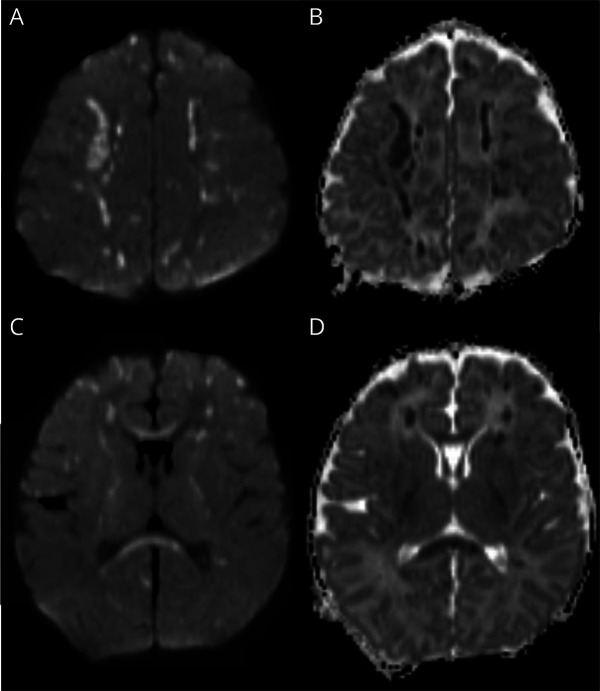

Background and objectives: DNA variations in the NF-kappa-B essential modulator (NEMO) gene are linked to incontinentia pigmenti (IP) and also immunodeficiency and autoinflammatory conditions. Some patients with IP present with neonatal vasculitis-like brain changes, although pathogenesis is unclear. We investigated cell-specific gene expression in a neonate with IP, who had encephalopathy, seizures, and vasculitis-like brain changes, and responded to steroid treatment.

Abstract Image